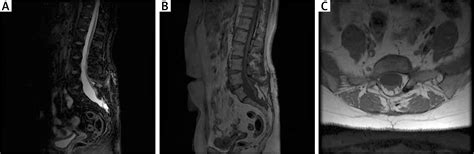

When Tethered Cord Symptoms are suspected, physicians utilize advanced imaging techniques to confirm the diagnosis. A physical examination is the first step, where doctors look for the previously mentioned skin markers or gait irregularities. To gain a clearer picture, the following diagnostic tools are commonly used:

• Magnetic Resonance Imaging (MRI): This is the gold standard for visualizing the spinal cord and determining the location of the tethering point.